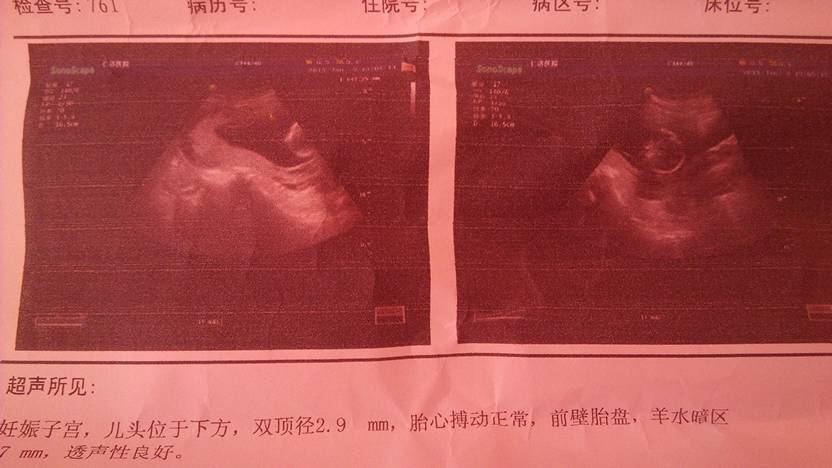

麻烦各位宝妈看看能不能看出来是男孩女孩 麻烦各位宝妈看看能不能看出来是男孩女孩 点击展开 让生活更美好_MiDF 2015-01-11 12:36 为您推荐: 其他回答 祝宝妈好孕 ι σ νêぷ瑄 2015-01-11 16:46 看不出来的 累呀 2015-01-11 15:51 看不出来。你没医生吗。 快乐宝贝,,,, 2015-01-11 15:37 看不出来吧。。。 泶荟嗳 2015-01-11 14:56 宝宝健康就好, ,,,,,,,,,, 2015-01-11 13:36 加载更多 相关问题 有没有能看的懂的宝妈帮忙看看是男孩女孩?谢谢了 二胎宝妈怎么没长妊娠线呢,大家看看这个肚子几个月了,猜猜男孩女孩?